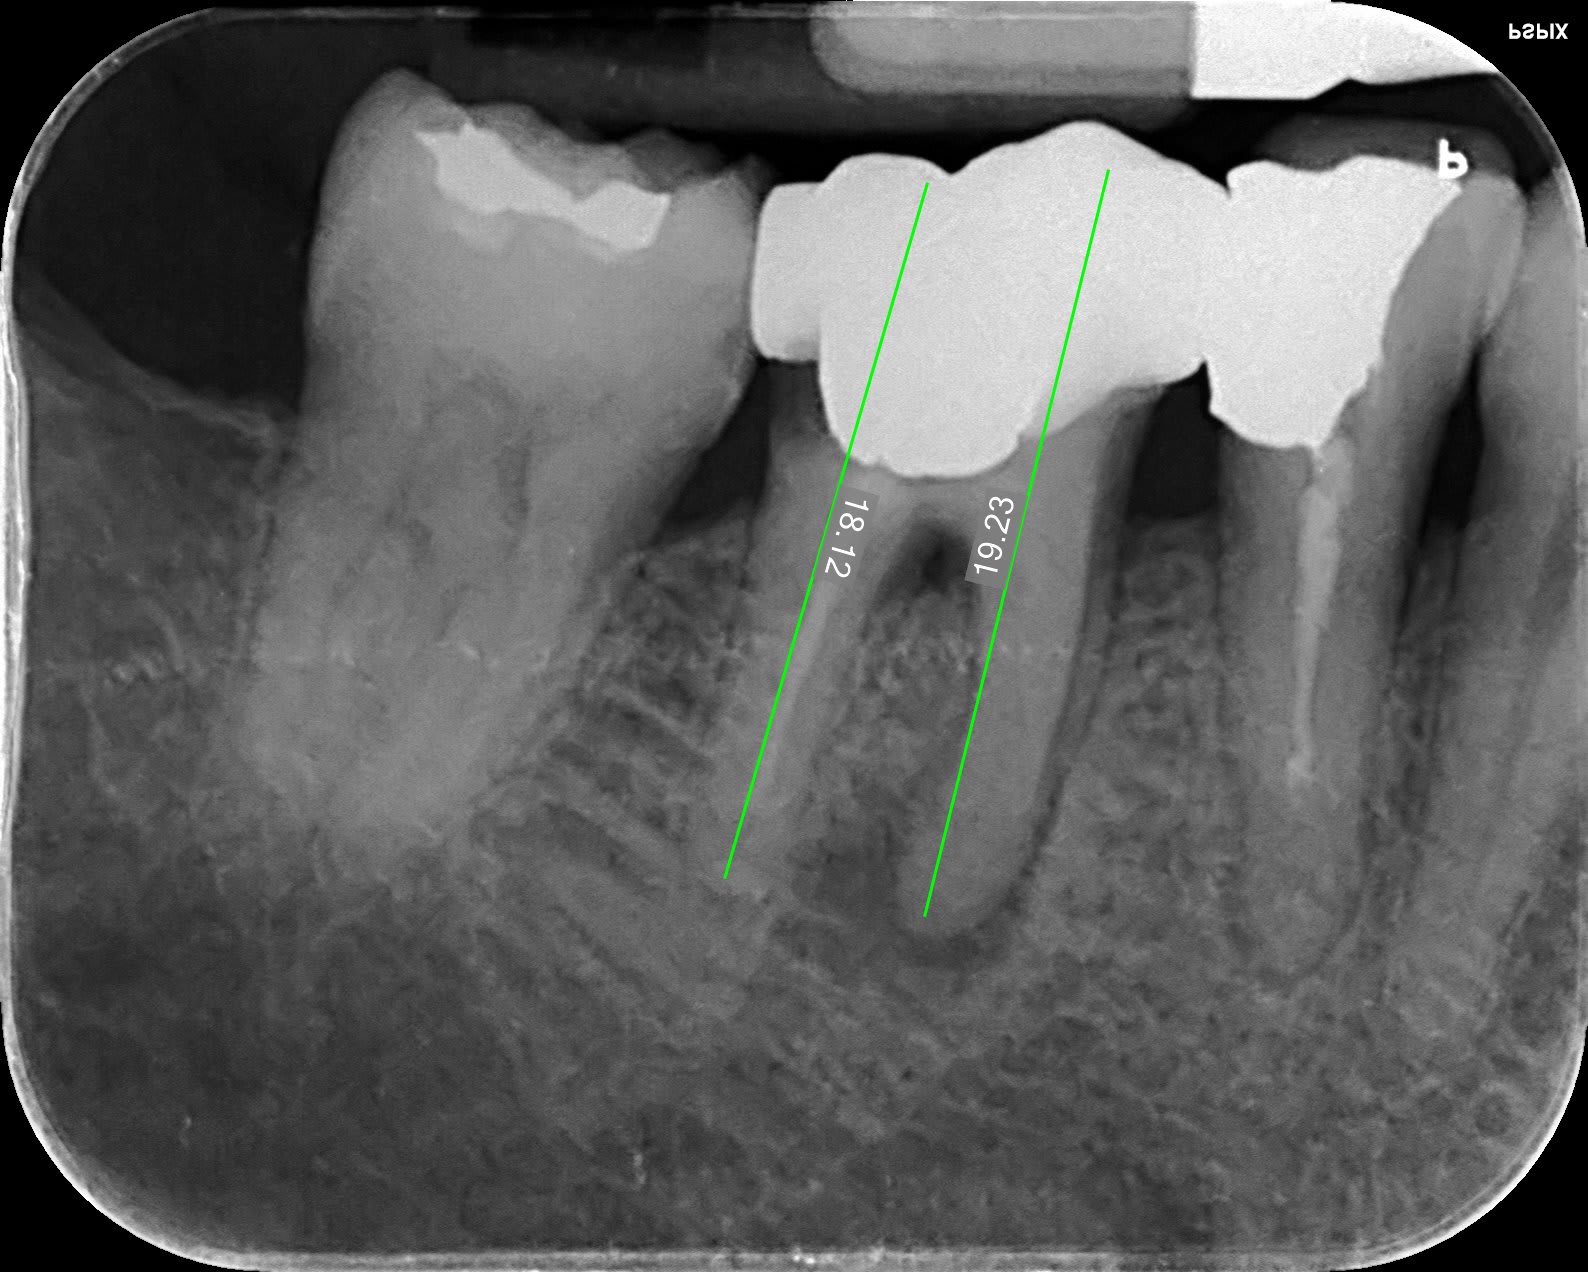

depuis le déconfinement j'ai l'impression de faire un DU d'endo:-)

47 iejkdr - Eugenol

T’en profiteras pour regarder l’occlusion mon Vulpi. Ça serait con d’avoir fait une belle endo pour rien . T’as passé le thermocompacteur ?

je sais faire que ça gutta condensor, bague bleue en 21mm. C'est plus rectiligne qu'il n'y parait et surtout c'est bien large ce qui aide, il n'y a que deux racines, M et D.

En fait, petit délire, j'avais le temps... que deux racines et patiente sympa... cone r25 racine M, finger spreader 3 cones 25 iso histoire d'avoir un bouchon et de ne pas dépasser, cone en D qui rejoint au dessus et gut cond.. est-ce rac0 compatible??? ça... ??